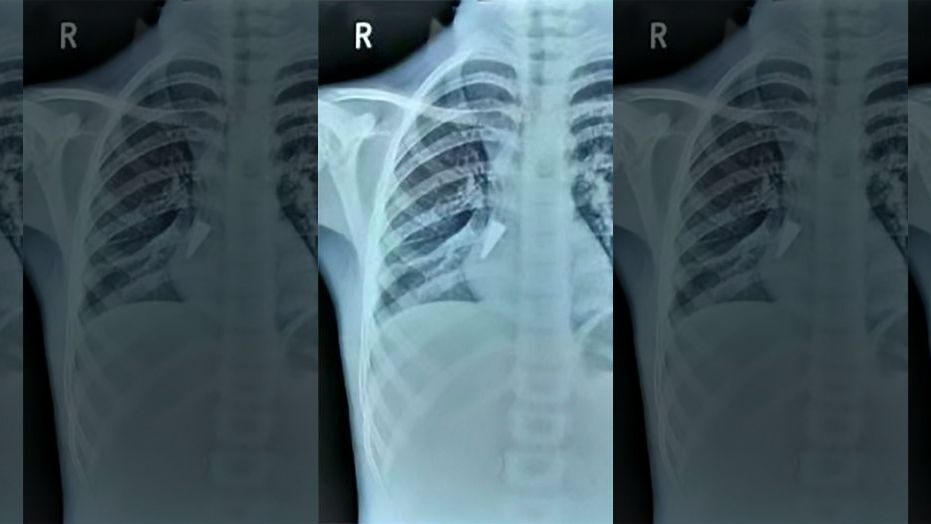

Little lungs in peril as pneumonia cases on rise